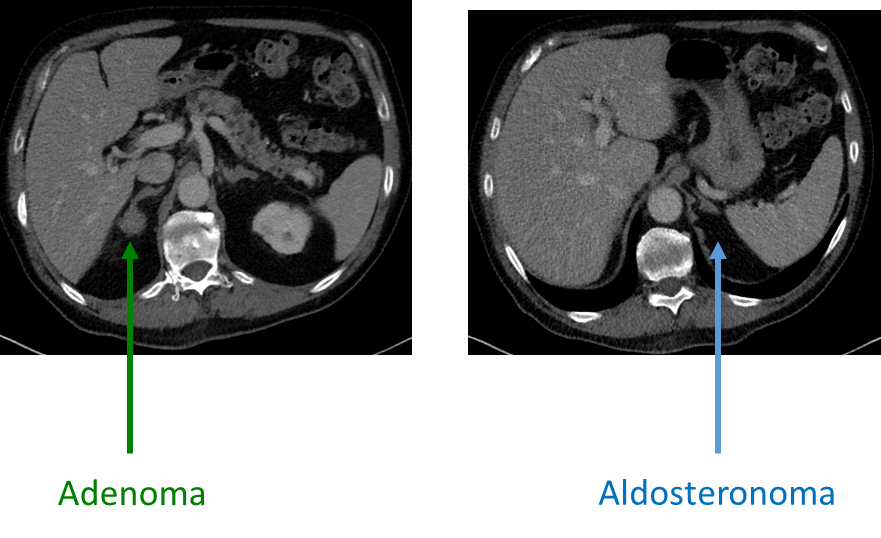

What is an Aldosteronomas?

Aldosteronomas or Conns Syndrome are tumors of the zona glomerulosa that causes hyperaldosteronism

1) Hypersecretion of aldosterone often leads to hypertension and hypokalemia due to rapid uptake of sodium and secretion of potassium and hydrogen

→ patients should have suppressed renin release

2) Most common cause of aldosteronomas are bilateral hyperplasia

→ patients with bilateral hyperplasia are unable to be surgically treated, and need to be treated with a aldosterone antagonist

→ unilateral tumors can be treated with resection